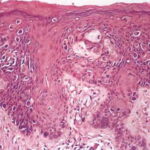

PATHOLOGY The intraepidermal adenocarcinoma of EMPD and MPD has a similar histologic appearance. There are groups, clusters, or single cells within the epidermis that show nuclear enlargement with atypia, prominent nucleoli, and well-defined ample cytoplasms . Intercellular bridges are absent. The cells can be within all levels of the epidermis and can compress but preserve the basal layer without junctional nest formation. The cells can extend into the contiguous epithelium of hair follicles and sweat gland ducts. Acanthosis, hyperkeratosis, and parakeratosis are often present. These cells have a “pagetoid” appearance and simulate other intraepidermal malignancies, including melanoma, pagetoid squamous cell carcinoma in situ, mycosis fungoides, cutaneous adnexal carcinomas (sebaceous carcinoma, porocarcinoma, and others), Merkel cell carcinoma, Langerhans cell histiocytosis, and other epidermotropic cutaneous metastases. The cells of MPD and EMPD can be pigmented, which should not necessarily indicate they are melanocytic. Paget's cells have intracellular mucopolysaccharides, with EMPD having a greater amount of mucin as compared

Immunohistochemistry is a useful adjunct in making the correct diagnosis. Low-molecular-weight cytokeratin stains cytokeratin 7 (CK7) and anti-cytokeratin (CAM 5.2) are sensitive markers for both MPD and EMPD . They are not completely specific, however, with both Toker and Merkel cells showing CK7 positivity. The cells of MPD and EMPD may stain with carcinoembryonic antigen and epithelial membrane antigen. The most useful keratin markers for Paget disease are CAM 5.2 and CK7, as they stain more than 90 percent of Paget's cells but do not react with epidermal or mucosal keratinocytes.13,14 The cells of pagetoid squamous cell carcinoma in situ typically do not stain with CK7 and CAM 5.2. S100 and HMB-45 are useful markers to exclude melanoma, as both are typically negative in MPD and EMPD. CK20 positivity has been found more frequently in cases of secondary EMPD with underlying carcinoma as compared to those cases of primary intraepithelial EMPD (CK7+/CK20-).15 Gross cystic disease fluid protein-15 (GCDFP-15) is a marker for apocrine epithelium and is typically positive in primary EMPD not associated with underlying neoplasm. In contrast, GCDFP-15 is frequently negative in those cases of secondary EMPD with an associated malignancy.16 Mucin core protein (MUC) expression is useful in the diagnosis of MPD and EMPD.17 MUC1 positivity is noted in both MPD and EMPD. MUC2 expression is generally negative in primary EMPD, but may be expressed in those cases of secondary EMPD with an associated underlying gastrointestinal adenocarcinoma. MUC5AC is frequently positive in primary EMPD and less commonly noted in secondary EMPD or those cases of primary intraepithelial EMPD that becomes invasive. SPECIAL TESTS Diagnosis of MPD and EMPD should be accompanied by a thorough search for underlying malignancy. Mammography is indicated in all cases of MPD, with biopsy of any underlying breast mass. In cases of EMPD, workup is directed toward the possibility of an underlying gastrointestinal or genitourinary neoplasm. Imaging of the abdomen and pelvis, colonoscopy, barium enema, cystoscopy, intravenous pyelogram, chest x-ray and mammogram (for the rare association of EMPD and MPD), and blood work are appropriate tests. Some reports have suggested that positron emission tomography scans may be useful for cases of invasive EMPD to evaluate for lymph node involvement and metastases. COMPLICATIONS Failure to identify and adequately treat cases of MPD can lead to metastatic disease with a poor prognosis. EMPD, if left untreated, can become invasive with a less favorable outcome. PROGNOSIS AND CLINICAL COURSE Overall survival in patients with MPD is affected by lymph node status and the presence of an underlying breast mass. Patients with negative lymph nodes have been shown to have a 10-year survival rate of 75 percent to 95 percent, whereas those with positive lymph nodes have a survival rate of 20 percent to 45 percent.4 Patients with a palpable breast mass have a 5-year survival probability of 35 percent to 51 percent, as compared to 75 percent to 82 percent in patients without a palpable mass. The prognosis for primary EMPD confined to the epidermis is excellent with appropriate treatment. Careful monitoring for early detection of local recurrence is critical given the multifocal pattern often present in EMPD. In contrast, invasive EMPD has a high rate of metastasis and carries a poor prognosis. The depth of invasion appears to be an important prognostic factor, with microscopic invasive disease (less than 1 mm) having a more favorable prognosis as compared to those with deeper invasion. Lymphovascular invasion and regional lymph node metastases markedly reduces overall survival rate and indicates a very poor prognosis. Clitoral EMPD has been shown to have a higher incidence of death from the disease as compared to other vulvar EMPD locations. In cases of secondary EMPD, the prognosis is related to the underlying carcinoma. TREATMENT Mammary Paget Disease Treatment of MPD is surgical. However, optimal surgical management of MPD remains to be defined, and treatment choice is frequently based on the presence or absence of an underlying breast mass. Mastectomy remains the standard definitive treatment. However, evidence suggests that MPD treated with breast-conserving surgery results in local control and survival rates similar to those achieved with mastectomy. Proper preoperative imaging is required to rule out multi-focal disease that would make breast-conserving therapy less effective and favor mastectomy. Lymph node evaluation via axillary dissection or sentinel lymph node biopsy must be considered in MPD. Adjuvant therapy with radiation, chemotherapy, or hormonal therapy is recommended based on lymph node status and specific features of the primary tumor. All diagnoses of MPD require referral to a physician with expertise in the management of breast cancer. Extramammary Paget Disease EMPD has been treated with a variety of different modalities. Although surgical management of the disease is the most frequently used method, various other treatments have a role for non-surgical candidates and as adjuvant therapy. SURGERY Surgery remains the treatment of choice for EMPD when tolerated by the patient. However, high local recurrence rates are seen after standard surgical excision, even with wide margins. This is most likely due to the irregular margins, multi-focal nature of the condition, and subclinical involvement of apparently unaffected skin. Several reviews have shown an overall recurrence rate of up to 44 percent with wide local excision, The local recurrence rates are higher in cases of invasive disease as compared to those limited to intraepithelial involvement. In addition, more radical and extensive surgeries are associated with lower rates of local recurrence. Patients with primary vulvar EMPD treated with radical vulvectomy, radical hemivulvectomy, and wide local excision have reported recurrence rates of 15 percent, 20 percent, and 43 percent, respectively. Multiple scouting biopsies to help delineate the extent of the disease before surgery can be a useful adjuvant technique.26 Intraoperative staining with CK7 is the preferred immunostain for intraoperative tissue evaluation.27 Sentinel lymph node biopsy has been described in the treatment of EMPD. Although this technique has been limited to a small number of reported patients and most cases of EMPD have in situ disease, sentinel lymph node biopsy may prove beneficial for those patients with increased risk of lymph node involvement and metastasis (i.e., dermal invasion of Paget's cells).29 MOHS MICROGRAPHIC SURGICAL EXCISION Given the high rates of local recurrence and the significant morbidity associated with radical and repeated surgeries, Mohs micrographic surgical excision (MMS) has been used to improve cure rates and for tissue sparing of critical genitourinary anatomic structures as compared to wide local excision.2,27,30,31 The recurrence rate after treatment with MMS has been reported as 16 percent for primary EMPD and 50 percent for recurrent EMPD. Ninety-seven percent of the cases treated with MMS required margins of 5 cm from the clinical tumor margin. However, if surgical margins of only 2 cm were used, as may be the case because wider margins may not be feasible when operating on the genitalia, only 59 percent of